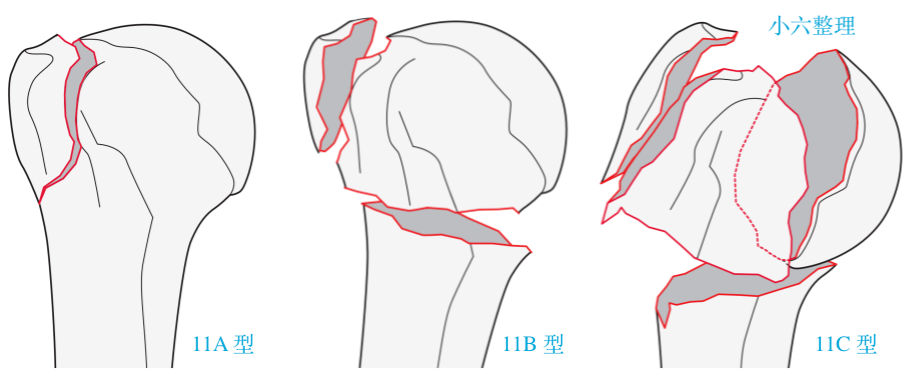

11 C 型:关节内,四部分骨折(解剖颈)。